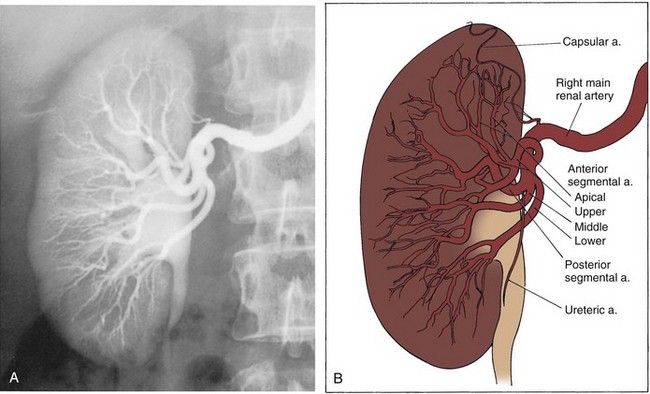

Upon approaching the kidney, the renal artery splits into four or more branches, with five being the most common. These are the renal segmental arteries (Fig. 1–30). Each segmental artery supplies a distinct portion of the kidney with no collateral circulation between them (Fig. 1–31). Thus occlusion or injury to a segmental branch will cause segmental renal infarction. Generally, the first and most constant branch is the posterior segmental branch, which separates from the renal artery before it enters the renal hilum. Typically there are four anterior branches, which from superior to inferior are apical, upper, middle, and lower. The relationship of these segmental arteries is important because the posterior segmental branch passes posterior to the renal pelvis while the others pass anterior to the renal pelvis. Ureteropelvic junction obstruction caused by a crossing vessel can occur when the posterior segmental branch passes anterior to the ureter causing occlusion. This division between the posterior and anterior segmental arteries has an additional surgical importance in that between these circulations is an avascular plane (see Figs. 1-26 and 1-31). This longitudinal plane lies just posterior to the lateral aspect of the kidney. Incision within this plane results in significantly less blood loss than outside this plane. However, there is significant variation in the location of this plane, requiring delineation before incision. This can be done with either preoperative angiography or intraoperative segmental arterial injection of a dye such as methylene blue.

Figure 1–31 Typical segmental circulation of the right kidney, shown diagrammatically. Note that the posterior segmental artery is usually the first branch of the main renal artery and it extends behind the renal pelvis.